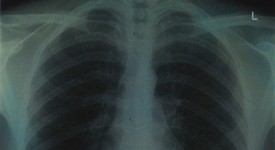

Amianto, perché è così pericoloso per la salute? In linea di massima la grande pericolosità dei manufatti contenenti amianto risiede nella possibilità che questi liberino le famigerate fibre, che possono essere inalate. In tal caso, parte di queste anziché essere inalate restano nei polmoni per tutta la vita.